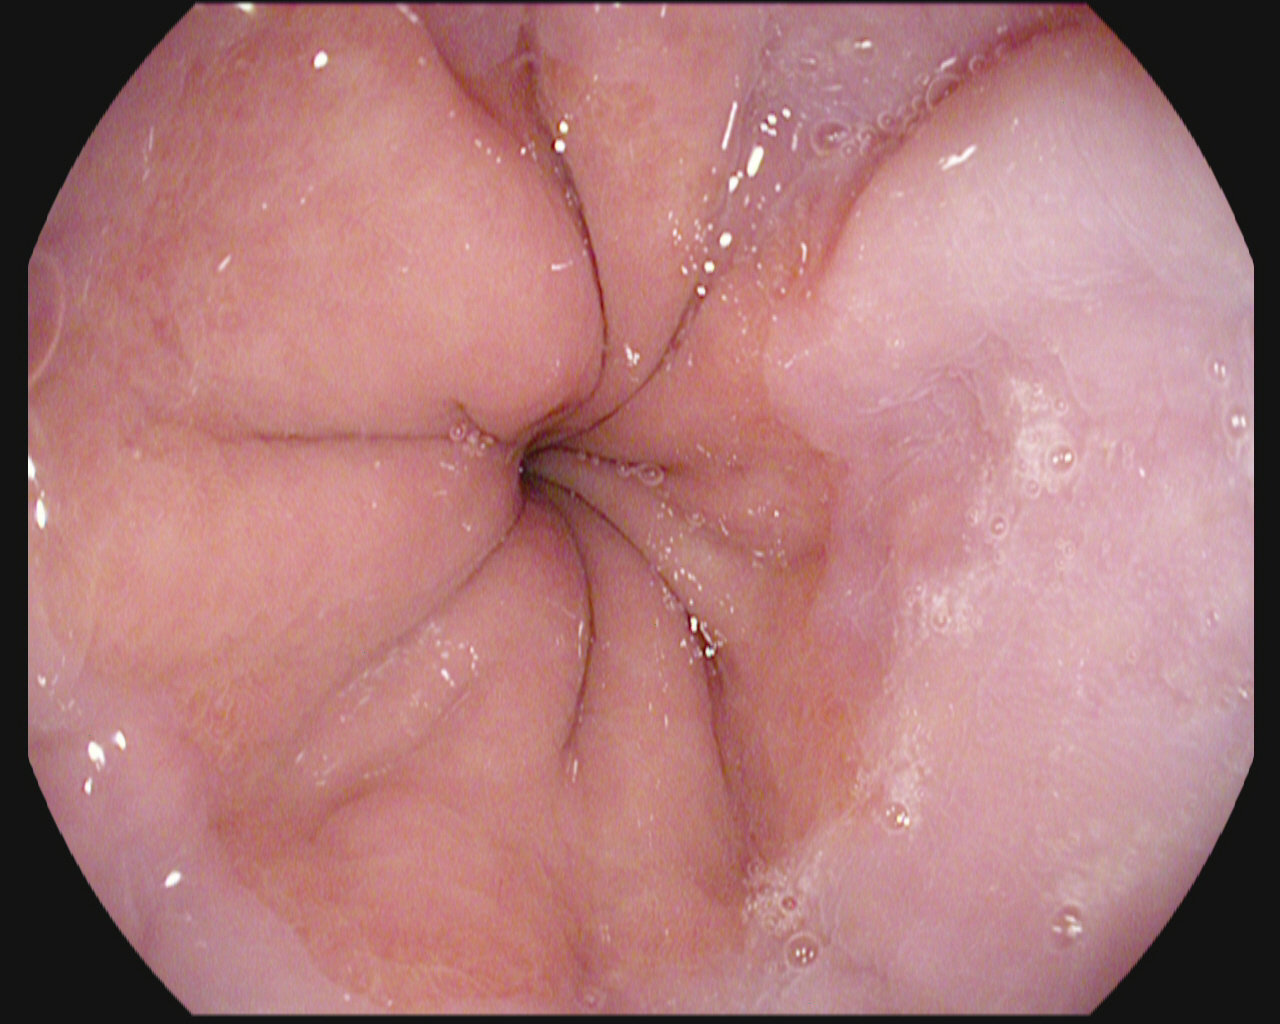

The gastrointestinal (GI) tract is prone to many different diseases

Doctors use sensor and image data to diagnose

The procedure's success is heavily dependent on the doctor

Image of a polyp from a colonoscopy

Gastroscopy and colonoscopy

We can use this data to train machine learning algorithms

In the medical field of Gastroenterology equipment for visualization of the gastrointestinal tract is used for diagnosis

The doctor's detection rate during examinations are heavily dependent on their experience and state-of-mind.

The generated data can be used with deep convolutional neural network models for assisting doctors by automatically detecting abnormalities and diseases.